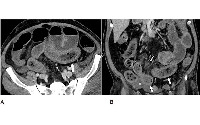

Imaging Reveals Bowel Abnormalities in Patients with COVID-19

Patients with COVID-19 can have bowel abnormalities, including ischemia, according to a new study published in Radiology.